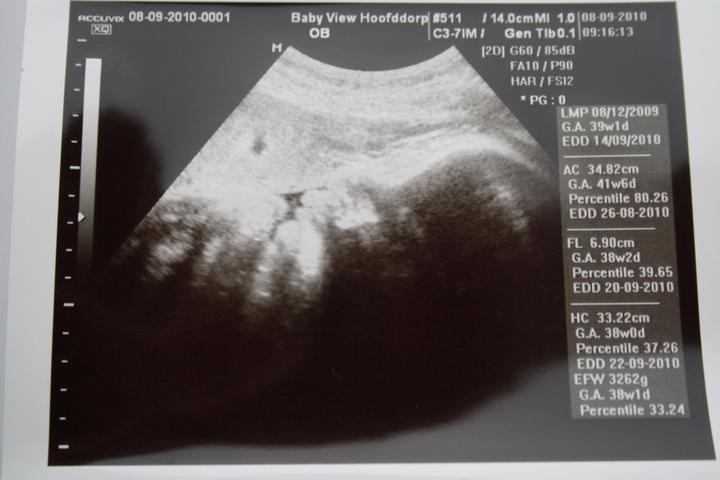

dnes sme boli na ultrazvuku, váha 3349g